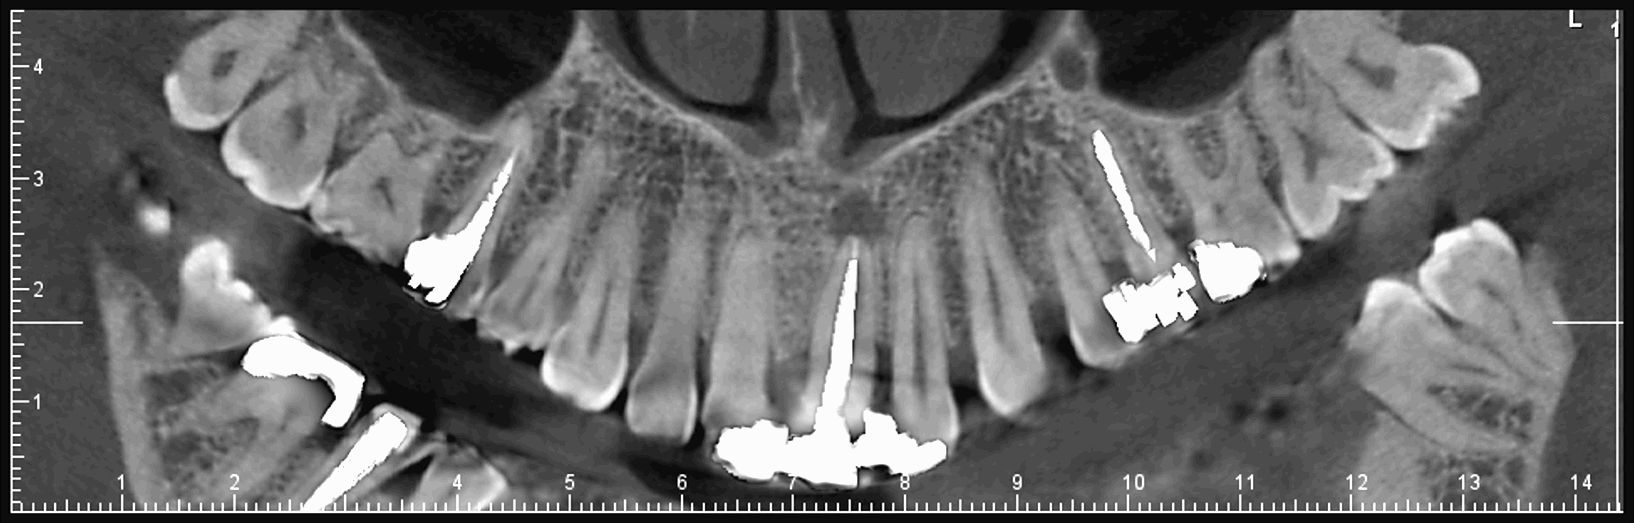

Le cone beam est une nouvelle technique de radiographie numérisée situé entre le panoramique dentaire et le scanner, il utilise un faisceau d’irradiation de forme conique d'où son nom. Cet appareil présente notamment l’avantage d’être plus précis que le panoramique dentaire et il possède une résolution similaire, voire supérieure à celle du scanner, avec en plus la possibilité d’une reconstruction numérique en 3D.

Il permet de balayer en un seul passage l’ensemble du volume à radiographier et en étant moins irradiant que le scanner.

Le cone beam utilisé en pathologie dentaire et maxillo-faciale est indiqué pour l’examen des tissus minéralisés (dents, cartilages, os), il permet d’identifier les lésions osseuses, les fractures, les infections, les kystes ou les corps étrangers.

Les nouvelles générations de scanner permettent de faire une acquisition d’un volume global d’une partie du corps et de travailler à l’intérieur de ce volume en isolant une structure anatomique donnée et de l’explorer dans tous les plans de l’espace.

Grace à la technique de seuillage il est possible de dissocier progressivement les dents des structures osseuses environnantes dans le volume donné.